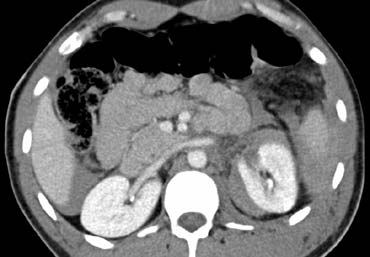

Bên trái là một biểu hiện phổ biến khác của chấn thương tụy.

Quan sát các hình ảnh và mô tả các phát hiện.

Sau đó tiếp tục.

Đây là tổn thương phối hợp theo vùng bên phải.

Có rách gan đi qua các mạch máu lớn kèm theo đứt ngang tụy tại vị trí nối giữa đầu và thân tụy.

Lực tác động phải đến từ phía trước bên phải, ép gan và tụy vào cột sống.

Đôi khi loại chấn thương này cũng liên quan đến tá tràng.